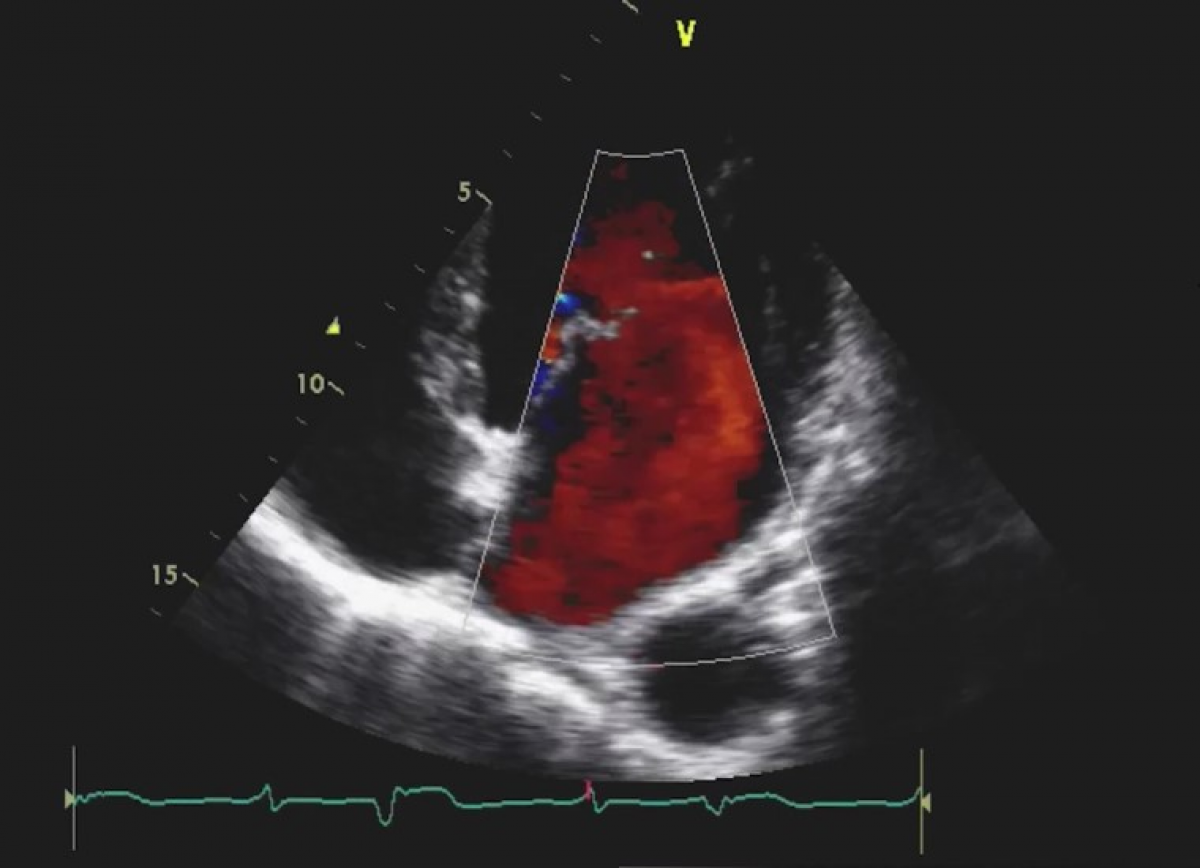

Pacjentka z zespołem Marfana

Zespół Marfana. Niedomykalność aortalna z istotnym poszerzeniem opuszki aorty.

Niedomykalność mitralna.

Echokardiografia przezklatkowa

Ocena niedomykalności aortalnej.

Ocena aorty piersiowej.

Ocena pacjentów z zespołem Marfana,